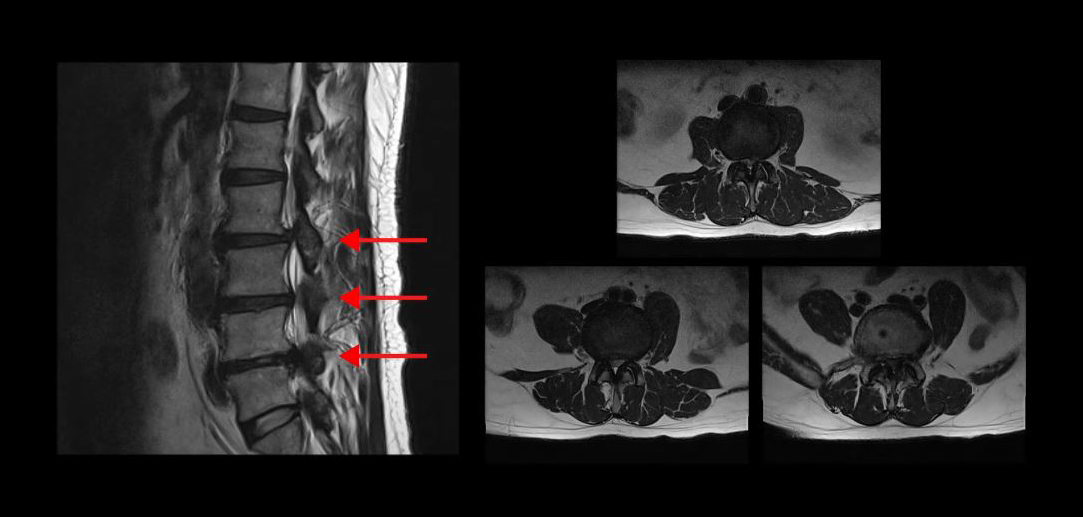

실제로 척추관이 심하게 막힌 환자분들의 케이스를 보여드리겠습니다

이분은 무려 세 마디의 척추관이 심하게 막혀있어서 거의 걷지 못하는 분입니다. MRI상 이렇게 세 마디의 척추관이 심하게 막힌 것이 보이실 겁니다. 이분은 무려 25년간 허리통증과 협착증 증상으로 고생하셨습니다. 그런데 서울 최상급 대학병원에서는 여러 마디가 안 좋으니 어려운 수술이고 수술의 실익이 없다는 말을 들으셨고, 서울 유명 척추전문병원에서는 세 마디를 한번에 수술할 수 없으니까 3주에 걸쳐 세 번의 수술을 하자는 말을 들으셨습니다.

또 다른 한 분은 척추관이 심하게 막혀있는 중심성 척추관협착증 환자분입니다. MRI를 보시면 한 마디가 심하게 막혀있죠. 이분은 10년 이상 협착증 증상을 앓다가, 결국 걷기만 하면 다리에 힘이 빠져버려서 아무데라도 주저 앉아야 하는 극심한 신경성 파행 증상을 겪으셨습니다. 서울의 유명 대학병원에서 수술을 하기로 했지만, 결국 심장 문제 때문에 수술을 못 받으셨습니다.